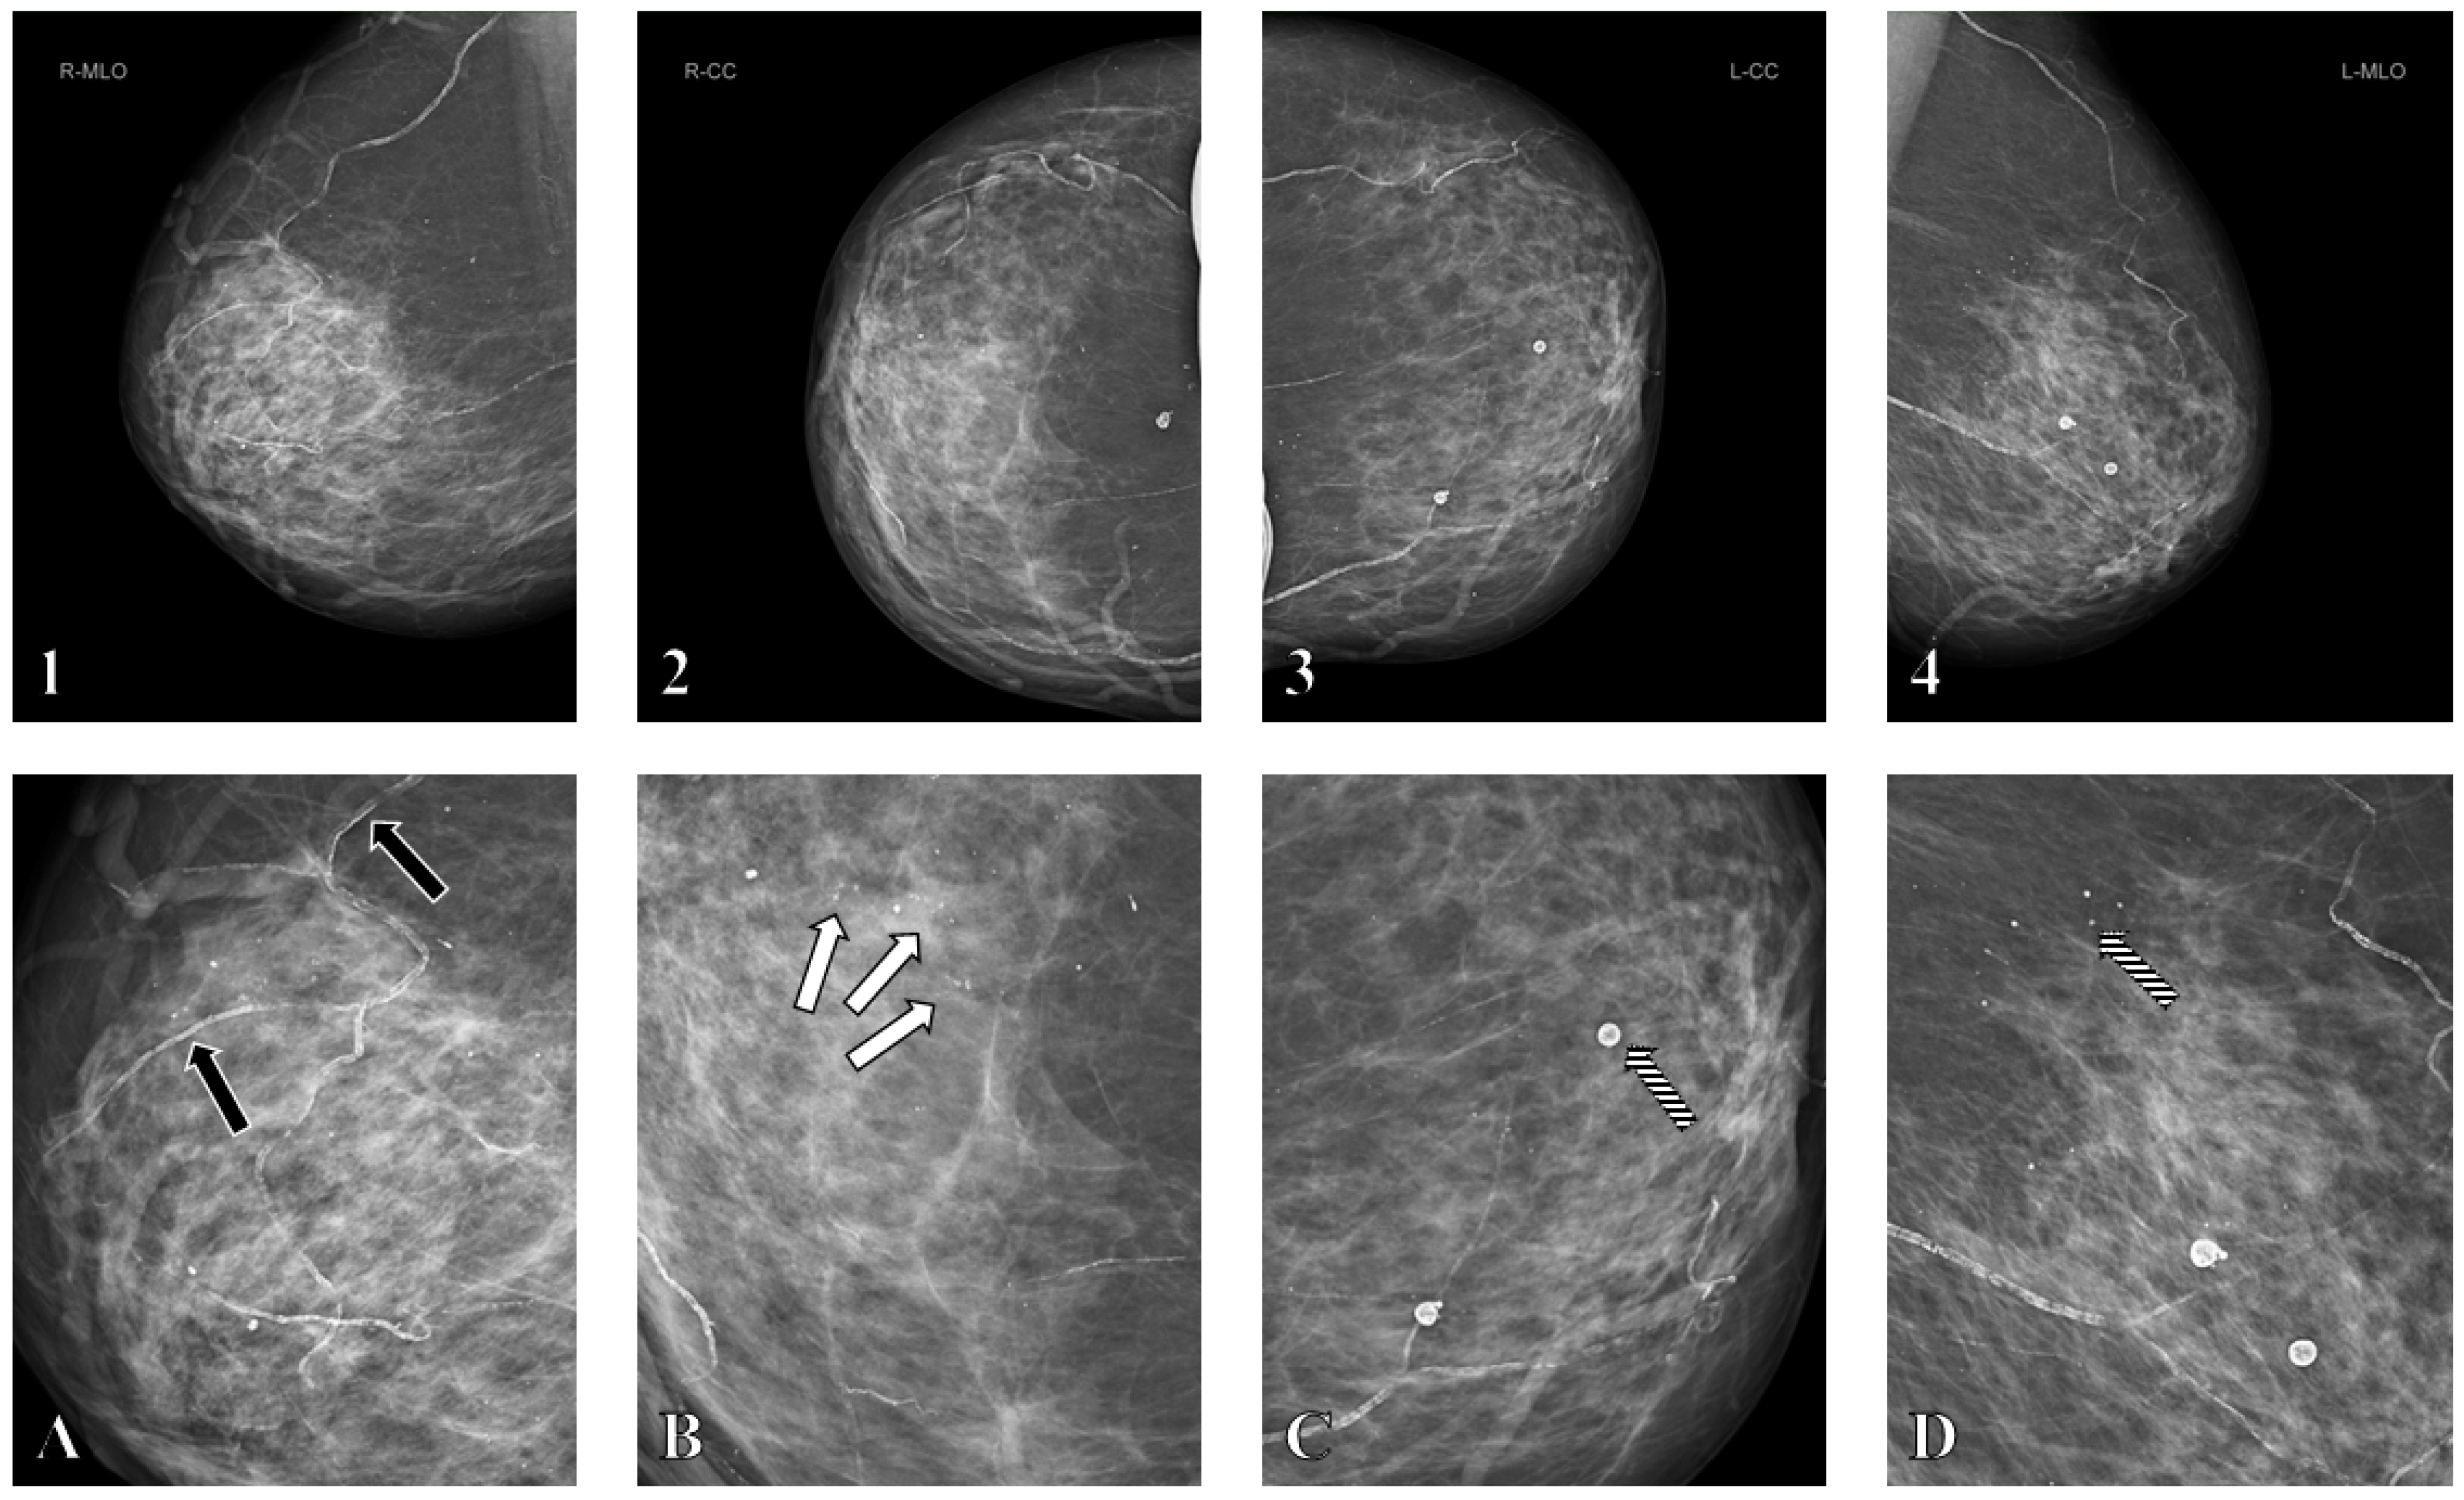

3.3. Mammographic Assessment and BAC Scoring

3.4. Multivariable Analysis